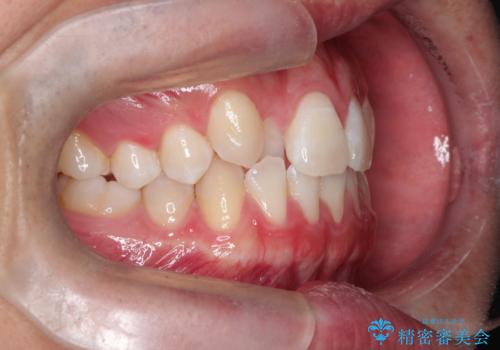

正中の改善と前歯の整列:抜歯を伴う矯正治療の症例

- 前歯のガタガタや正中の不整を改善するために、右上4、左上4、左下4を抜歯し、矯正治療を行いました。この治療により、見た目だけでなく、咬合のバランスも改善され、患者様の口腔内の健康が向上しました。